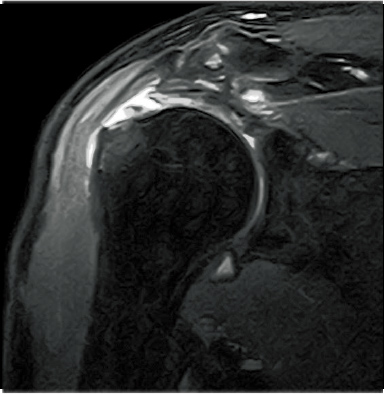

FatSep-T2WI